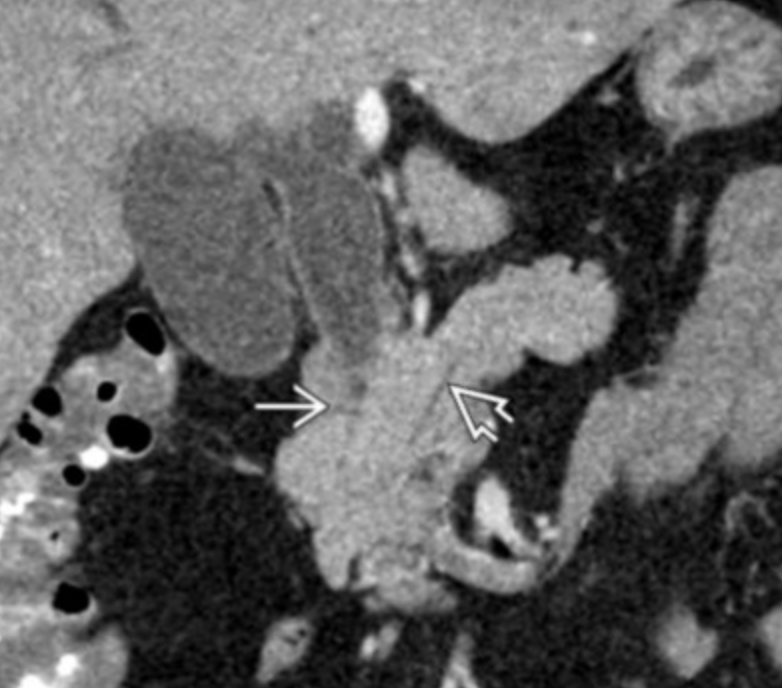

Klatskin Tumor (Hilar Cholangiocarcinoma)

• Typically at bifurcation of common bile duct

• Findings

• Intrahepatic biliary ductal dilation

• Mass at liver hilum